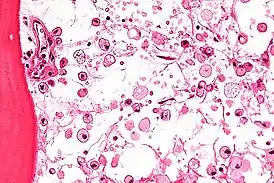

![]() На микрофотографии характерные изменения строения костного мозга при болезни Гоше — цитоплазма макрофагов напоминает смятую папиросную бумагу. Окраска гематоксилином и эозином | |